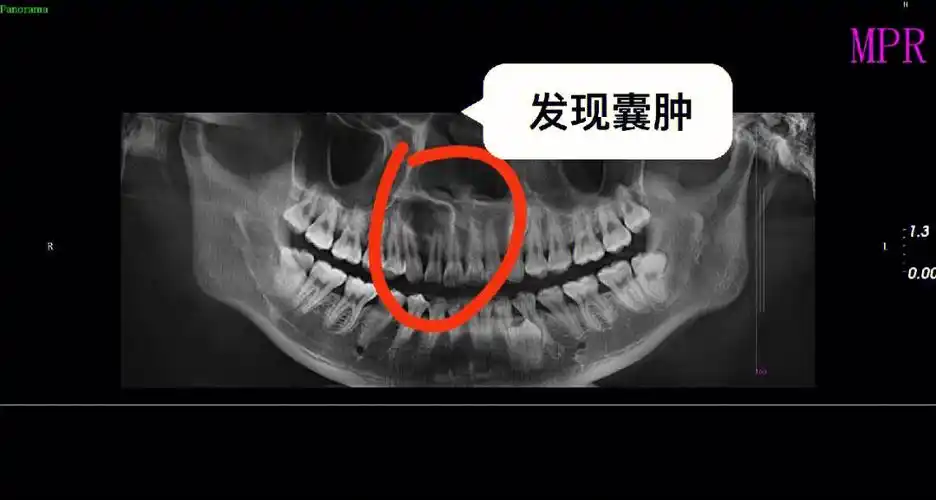

骨壁跟鸡蛋壳一样薄zo下牙槽神经清保留的第二磨牙wl被囊肿累及不能

牙齿根尖囊肿应该引起注意

左上颌前牙区囊肿一例